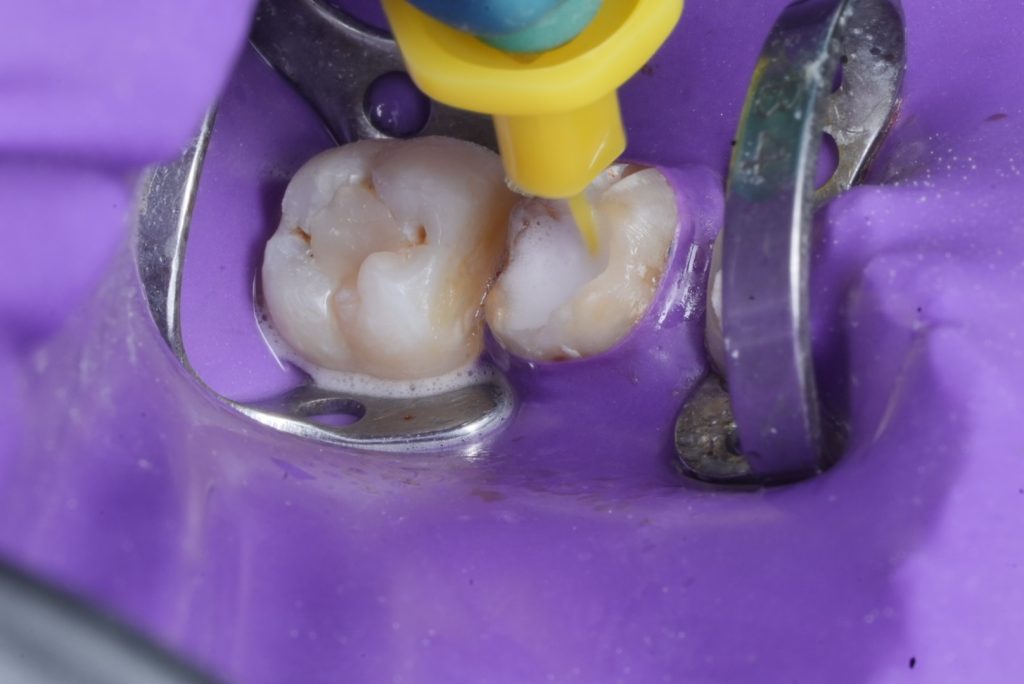

5. Core Build-Up and Preparation

A dual-cure resin core (Clearfil DC Core Plus) was bonded using 4th-generation adhesive (Clearfil SE Bond 2). Tooth preparation followed the principles of adhesive ferrule preservation with rounded internal line angles (Fig 2).

- Fig 2: Post-endodontic core build-up and crown preparation.